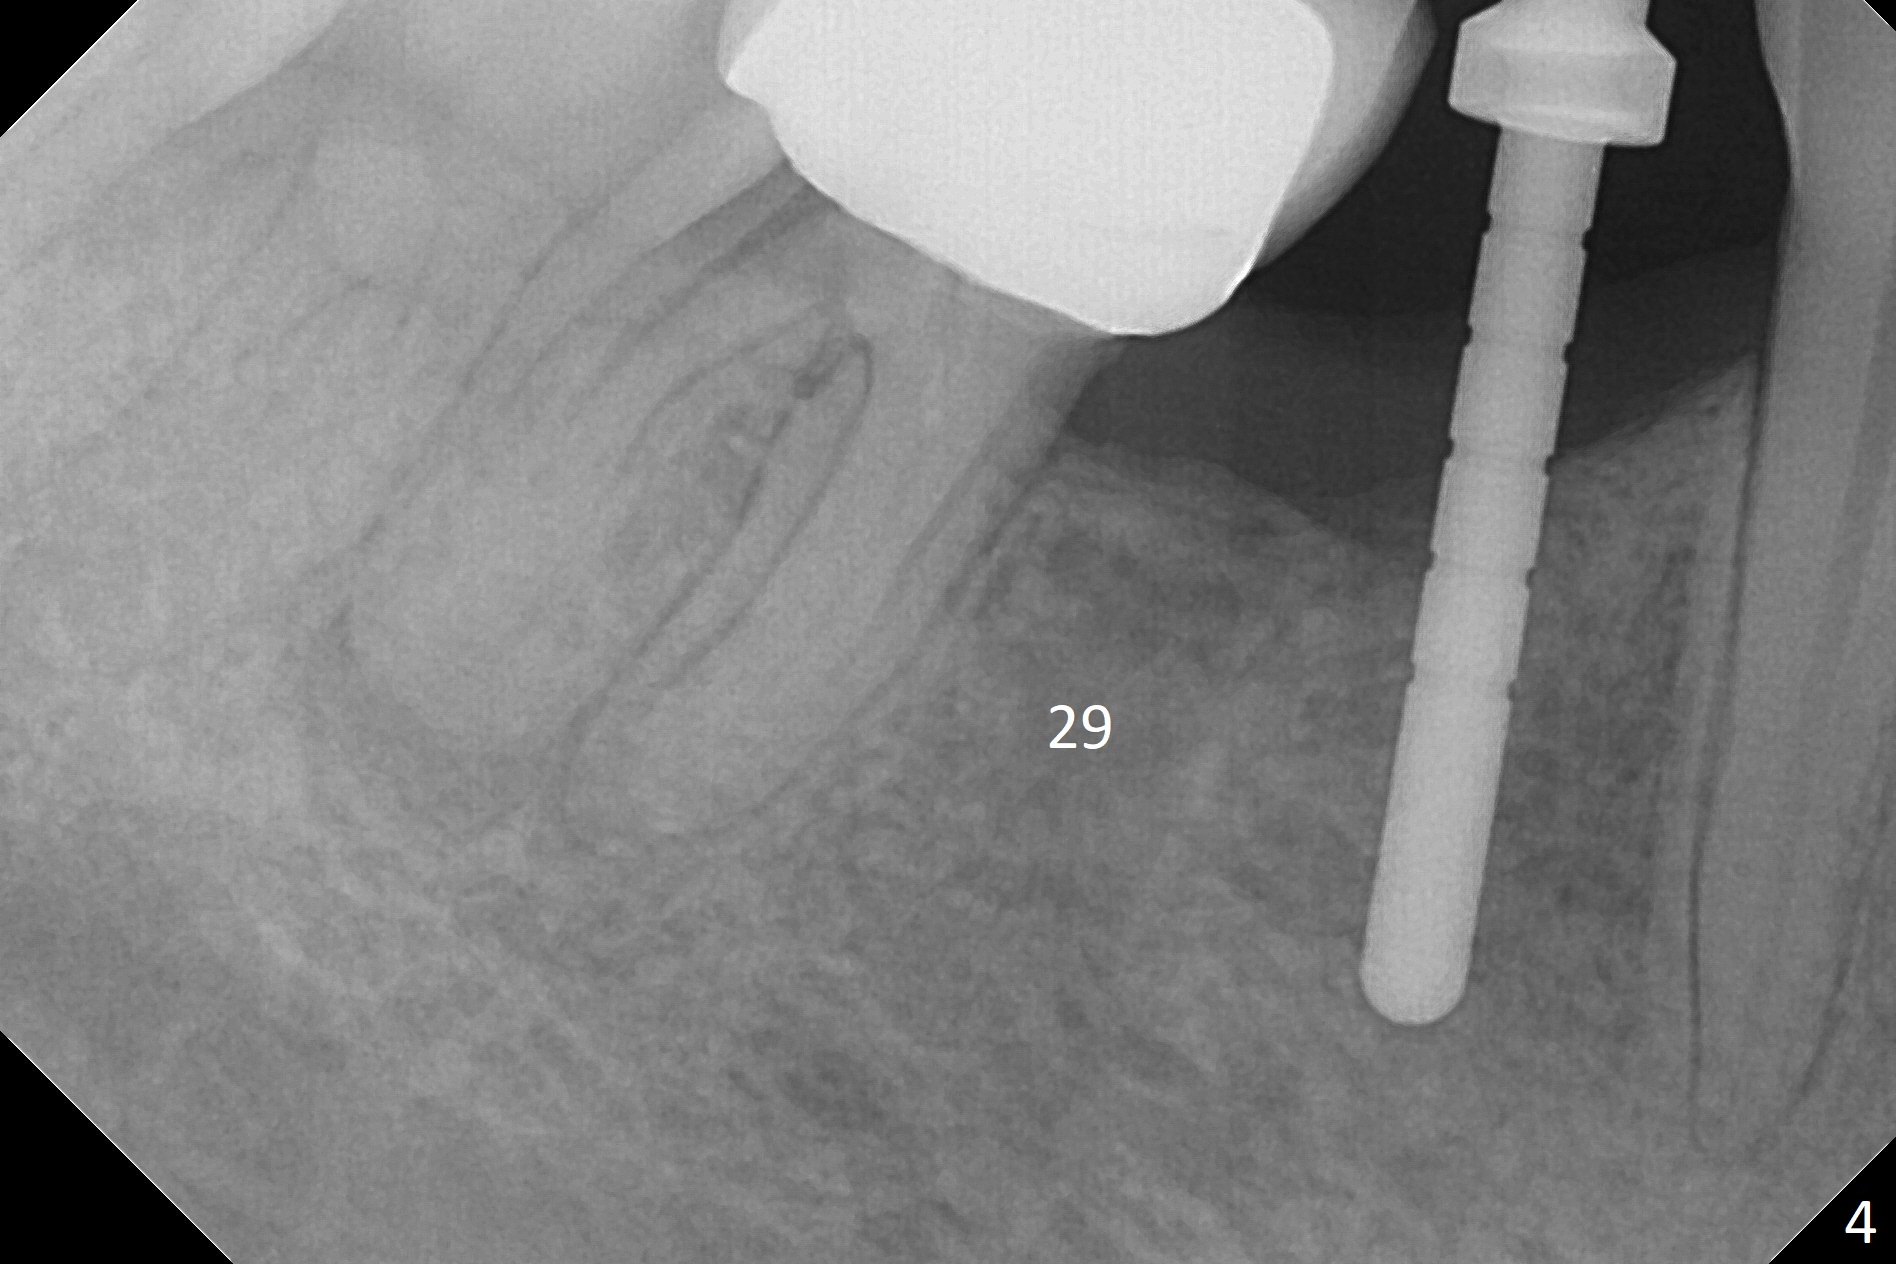

The patient returns for implant placement 11 months post extraction of #28 and 29. With flapless manner, initial osteotomy happens to drop into the original socket of #28 (Fig.4). After use of 3.3 mm Magic Drill (MD) and Final Drill for 15 mm, a 4x11 mm dummy implant is placed (Fig.5). It appears that the implant is long for the site (red dashed line: Mental Loop). However, a definitive implant (4x9 mm, IBS) has difficulty to reach its depth (Fig.6). After several rounds of untorque and retorque, the implant does not seat completely (Fig.7, implant driver disengagement) with autogenous bone placed distal (>). Retrospectively, a larger MD should have been used (3.8 mm) for complete seating in the dense bone. In fact she is post breast cancer treatment with 50% chance of relapse. The patient returns for follow up 1.5 months postop (Fig.8). The wound has healed. Impression is taken 5 months postop (Fig.9). When the crown is cemented, food impaction is an issue between the implant crown and crown at #30. Since the tooth #30 is mesially tilted with distal open margin and apical infection, the tooth will be extracted. Osteotomy is going to be initiated in the mesial slope of the mesial socket (Fig.9 red line). An implant will be placed more or less in the mesial socket (green box).